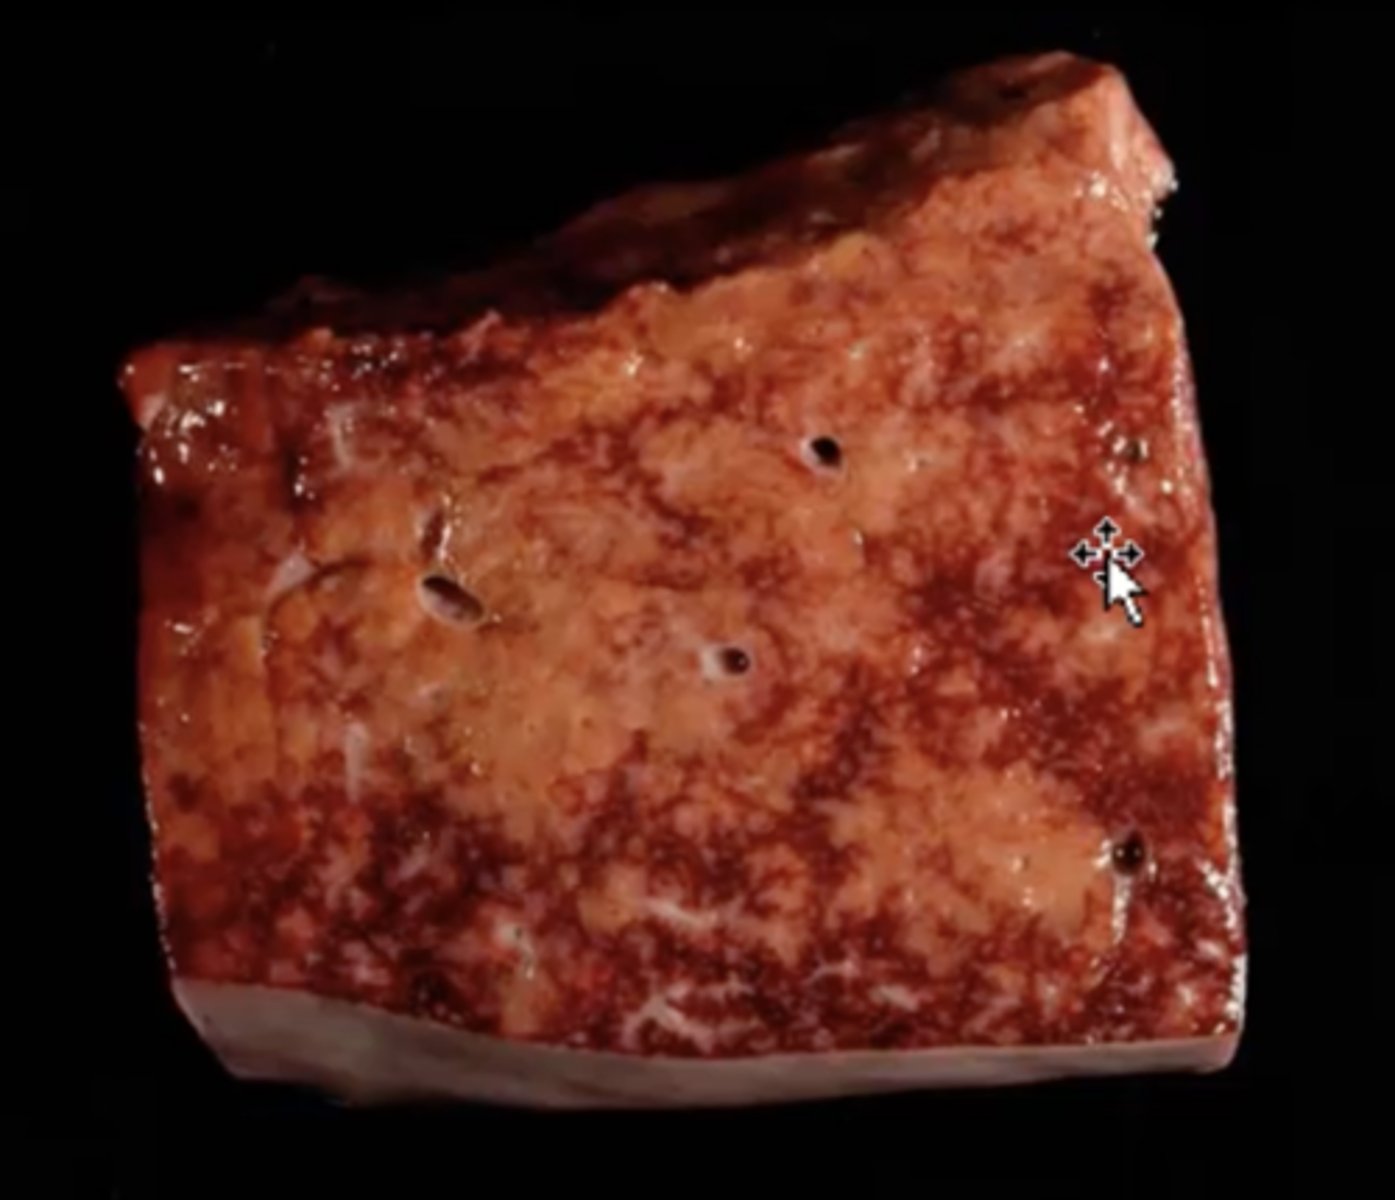

Chronic passive congestion

-NUT MEG LIVER

-branching fibrosis

-centrilobular fibrosis

-result of right-sided heart disease

-result of hypoxia

What has caused this gross appearance of this liver?

Chronic passive congestion

What has caused this gross appearance of this liver?

Chronic passive congestion

-classic Nut Meg liver

-brnahcing fibrosis + hepatocellular loss

What has caused this gross appearance of the liver?